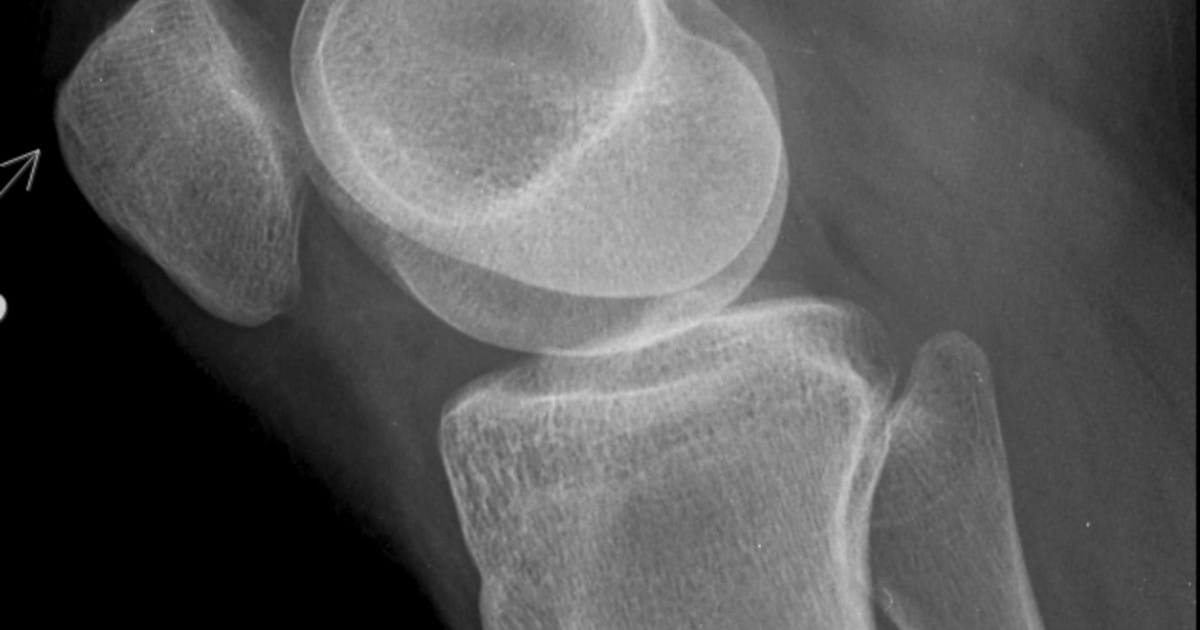

La artrosis de rodilla, o gonartrosis, es una enfermedad frecuente y degenerativa que consiste en la pérdida o desgaste excesivo del cartílago articular en una o más zonas de la rodilla.

El cartílago es un tejido firme encargado de recubrir y proteger todas las articulaciones. En la rodilla se acostumbra a deteriorar habitualmente, y de forma gradual, por múltiples razones al tratarse de una articulación de carga.